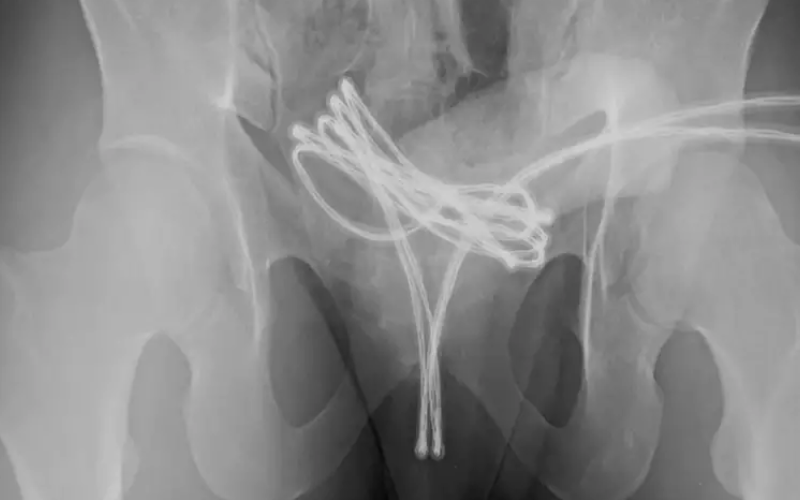

O paciente sofreu apenas ferimentos leves e recebeu alta após tratamento com antibióticos, analgésicos e o uso de um cateter urinário por uma semana (Foto: Cureus)

Um estudante universitário de 21 anos foi internado em um hospital após inserir um cabo de carregador no próprio pênis com o objetivo de obter prazer sexual. O caso foi descrito em um artigo publicado em fevereiro pela revista médica Cureus, dos Estados Unidos.De acordo com a publicação, o jovem revelou que, outras vezes, já havia inserido outros objetos na uretra, como cotonetes e cabos metálicos, para estimulação sexual. No entanto, essa foi a primeira vez em que não conseguiu removê-lo sozinho e precisou de atendimento médico. “A autoinserção de objetos na uretra por razões sexuais ou outras é rara, mas pode causar danos graves”, alertam os autores do artigo.

Após tentativas fracassadas de remoção manual, foi necessário realizar uma cirurgia sob anestesia geral. O procedimento consistiu na introdução de uma câmera pela uretra para localizar e retirar o cabo com o mínimo de danos possíveis.

O paciente sofreu apenas ferimentos leves e recebeu alta após tratamento com antibióticos, analgésicos e o uso de um cateter urinário por uma semana. Exames posteriores confirmaram que ele se recuperava bem e sem sequelas permanentes.Riscos da práticaA prática de inserir objetos no canal da uretra para estímulo sexual é conhecida como “sounding” — ou sondagem, em português. Apesar de haver quem a realize como forma de prazer, trata-se de uma atividade arriscada, que pode causar lesões graves no pênis.Especialistas alertam que a introdução de objetos na uretra pode provocar infecções, hemorragias, disfunção erétil, perfuração da bexiga e até sepse — uma infecção generalizada com risco de morte. O risco é ainda maior quando os objetos não são devidamente higienizados, favorecendo a contaminação por bactérias e infecções sexualmente transmissíveis (ISTs).